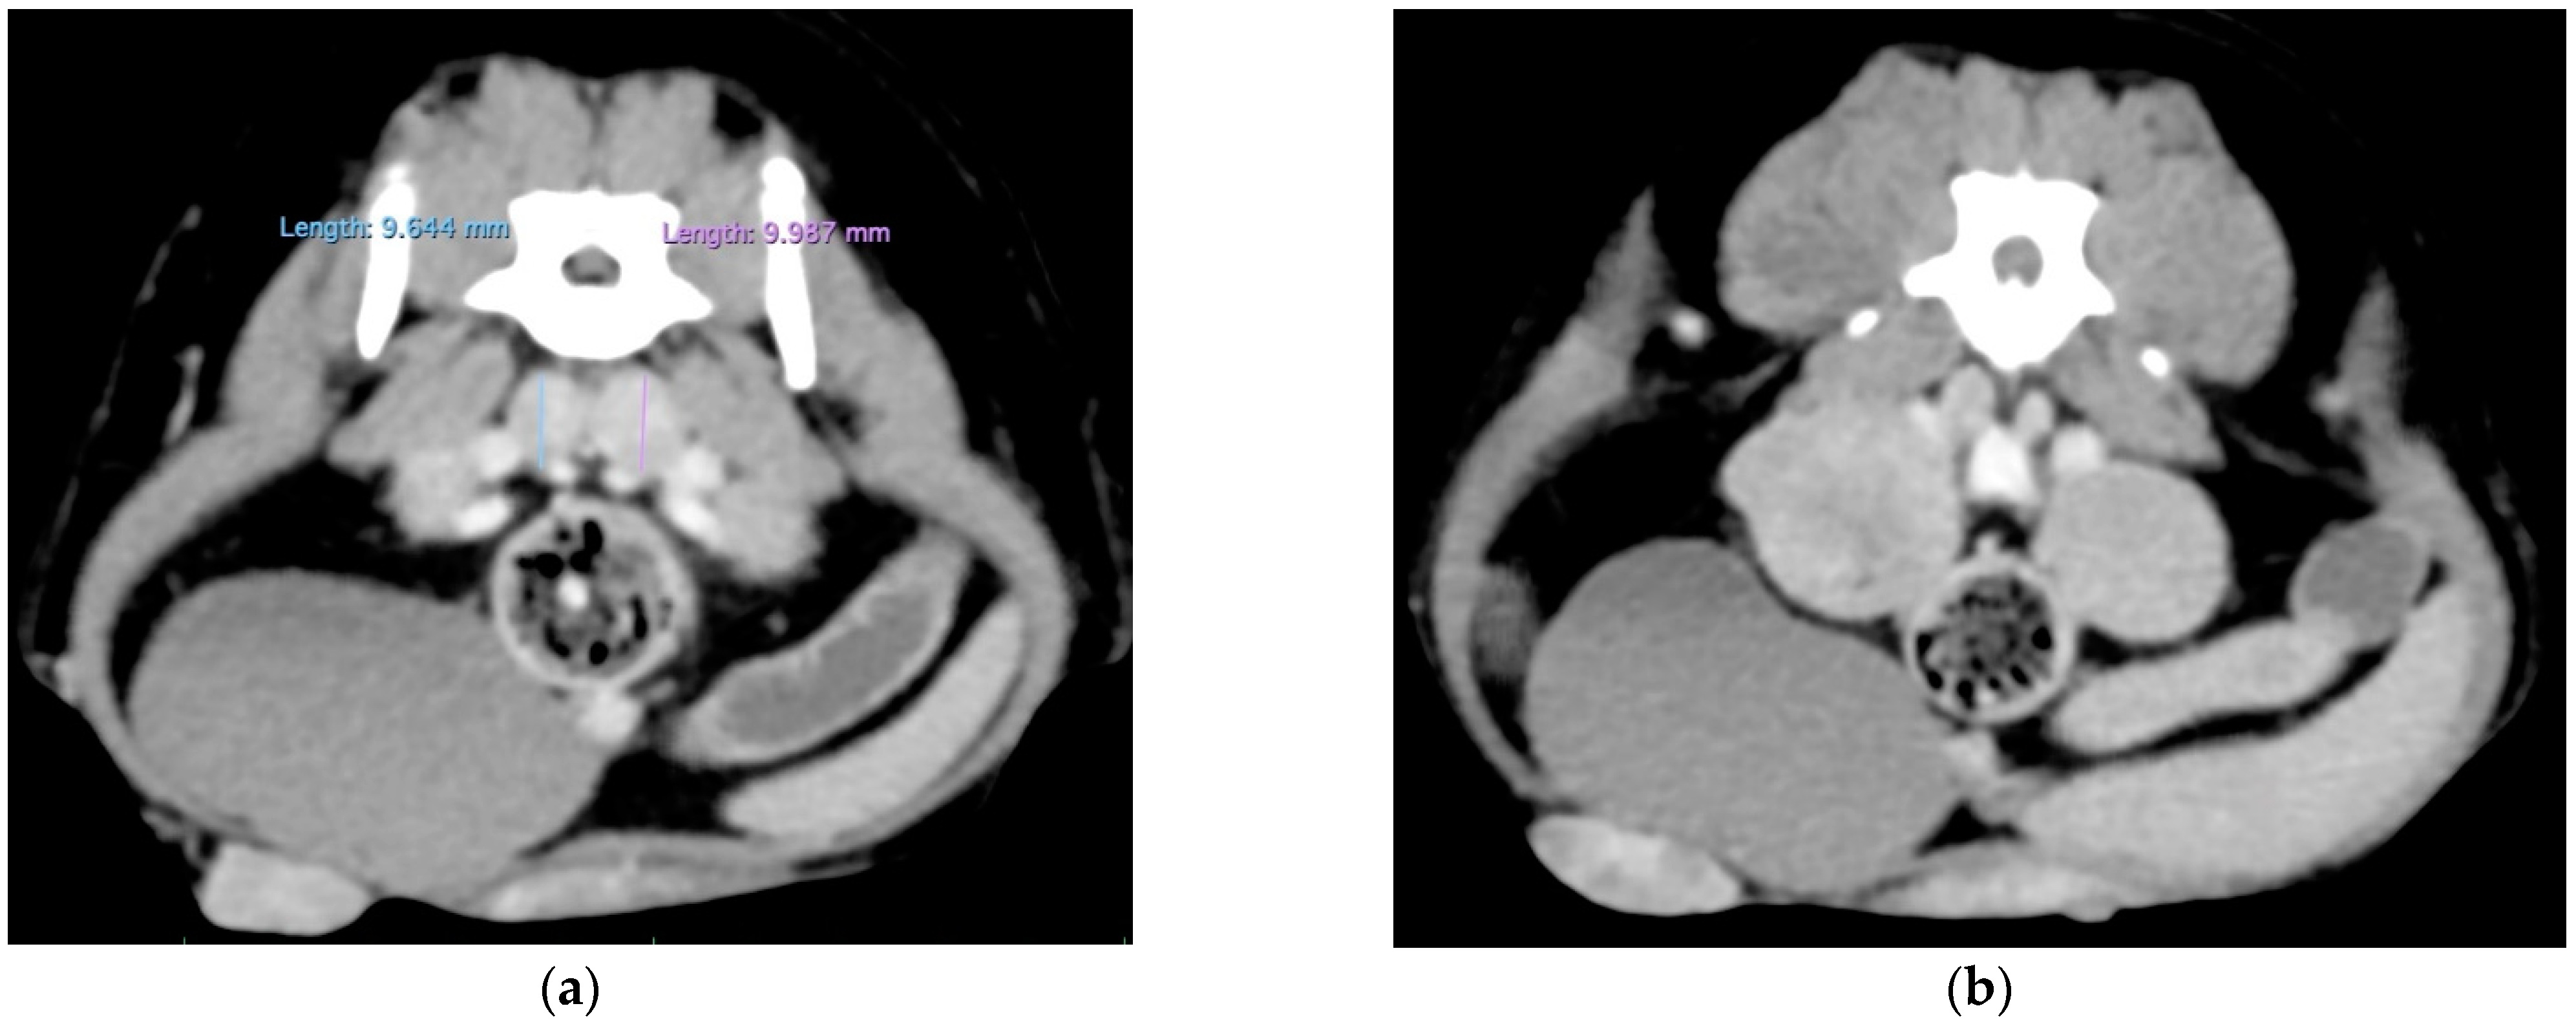

3.2. Additional Medical Tests

| 1 September 2021 | flaccid tail, evolving into posterior paresis within 24 h, spinal metastasis (CT examination) | ||||||||